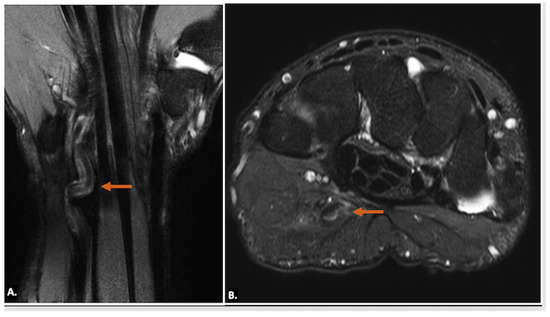

Other pathological conditions affecting Guyon’s canal include vascular abnormalities such as arteriovenous malformation (Figure 15), ulnar artery thrombosis, tortuosity (Figure 16), or aneurysms. Ultrasound imaging will show hypoechoic or anechoic mass with vascular flow seen on Doppler imaging in cases of aneurysm with absence of flow in a case of thrombosis. On MRI, thrombosis is seen as low or high signal intensity within the vessel lumen on both T1- and T2-weighted images, depending on duration. Aneurysms appear as well-circumscribed lesions, potentially with signal voids due to high flow. Pseudoaneurysm will show the presence of adjacent soft-tissue mass in close approximation with the lumen [23].

Figure 15.

(A) T1-weighted axial, (B) T2-weighted, fat-suppressed axial, and (C) T2-weighted, fat-suppressed coronal MR images of an arteriovenous malformation (indicated by the orange arrow) in the region of Guyon’s canal. The lesion appears hypointense on the T1-weighted sequence (A), appears hyperintense on T2-weighted, fat-suppressed sequences, (B) and demonstrates continuity with vessels (blue arrows) (C).

Figure 16.

(A) T2-weighted, fat-suppressed coronal and (B) T2-weighted, fat-suppressed axial MR images reveal the tortuous irregular path of the ulnar artery (orange arrow) in the region of Guyon’s canal, resulting in ulnar neuropathy and causing neuropathic symptoms.